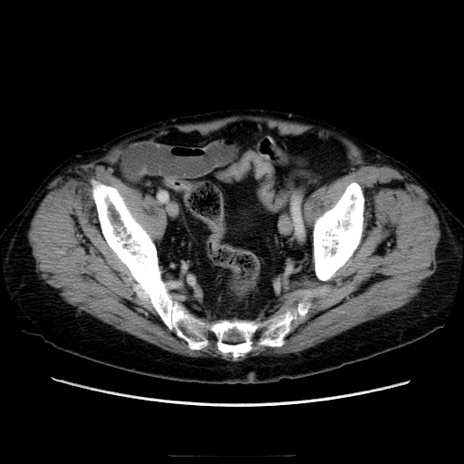

冠状断像

【症例】70歳代男性

【主訴】腹痛

【現病歴】肝硬変・肝細胞癌にてかかりつけの方。約9時間前に食後より腹痛出現。症状が徐々に増悪し、嘔吐出現したため来院。

【既往歴】肝硬変、肝細胞癌(RFA、TACE後)

【身体所見】意識清明、表情苦悶様、BT 36℃、BP 129/78mmHg、P 88bpm、SpO2 97%(RA)、右上腹部から心窩部にかけて圧痛あり、反跳痛なし、筋性防御あり。

【データ】WBC 5800、CRP 0.16